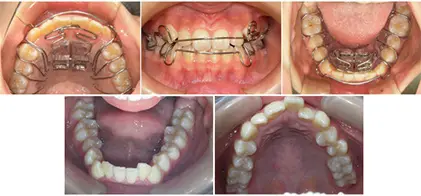

SHA(SH療法で使用される装置について)ドイツと日本にて特許を取得したSlidexという弾性のバネを使用した新しい顎拡大装置です。

SH療法で使用する装置=SHA(SHアプライアンス)